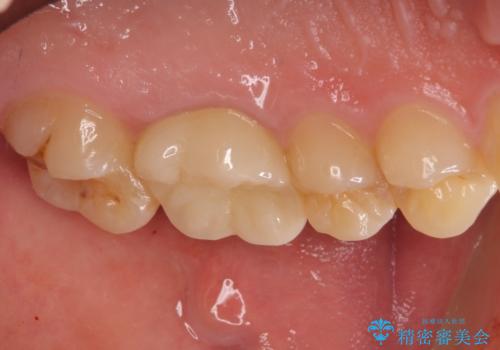

前医での処置後、治療前には気にならなかった痛み続いていたようですが、当院での処置後は痛みが徐々に引いていき、治療から半年が経過した時点では全く違和感も感じなくなりました。

根管治療後のクラウンも、まるでもとの自分の歯のように自然な仕上がりとなり、患者様には大変満足していただけました。